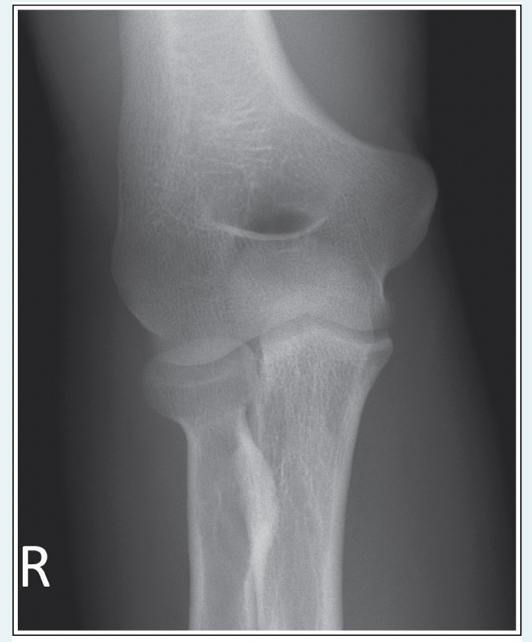

Which, from the following list of image criteria, is not met with this AP elbow image?

a.CR is not perpendicular with the IR

b.Hand is supinated

c.Equal demonstration of humerus and forearm

d.Arm is not extended

A